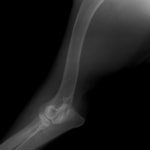

症例:柴犬 3歳

左後肢の完全挙上を主訴に来院されました。触診にて近位足根関節の過伸展を、レントゲン検査にて左足根関節周囲の軟部組織の腫脹、ストレス撮影によって距骨・踵骨と第4足根骨・中心足根骨間の脱臼および過伸展を認めました。

術前正面像左関節の腫れ

左足根関節の軟部組織が腫脹しています。

術前正面像

術前側面像屈曲位

術前側面像伸展位